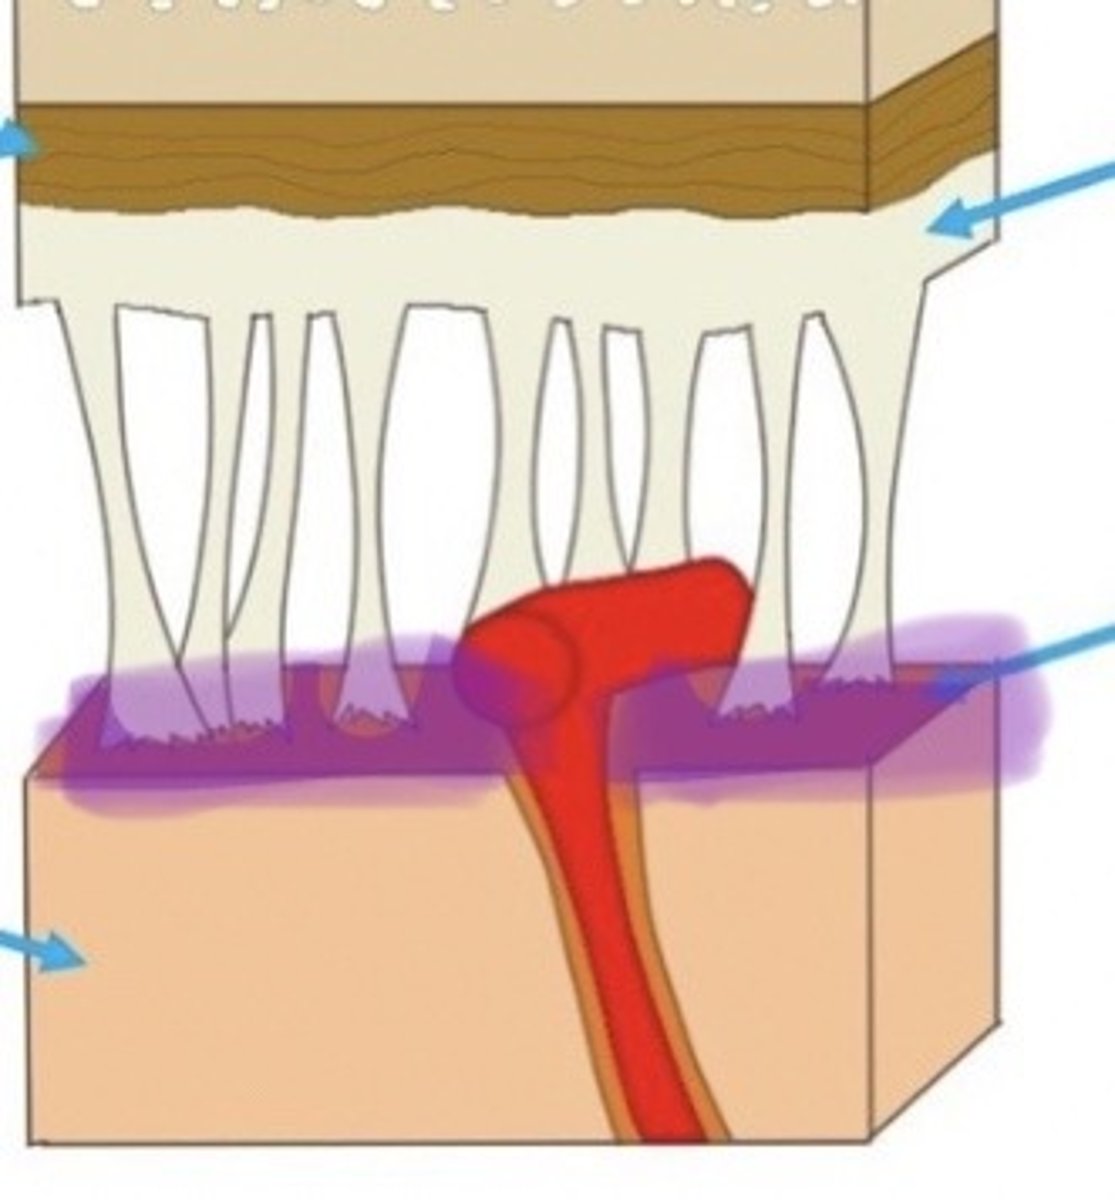

Meninges

The three protective membranes

-dura mater

-pia mater

-arachnoid

Dura Mater

Arachnoid Mater

Pia Mater

Sheep Dura Mater

this is a thin, cotton-like connection between the dura & pia mater, this is dissolved in the preservative & not visible in the brain we dissect

Arachnoid layer in Sheep